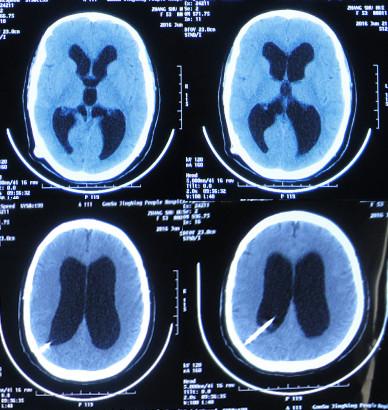

患者2014年6月20日出现持续头晕的症状,不能自行缓解,于2014年6月24日和6月26日分别就诊于甘肃省平凉县某医院和陕西省西安某医院,进行了头颅MRI和头颅CT示脑室扩张,脑积水(图-1、图-2)。

图-1:2014年6月24日头颅MRI

图-2:2014年6月26日头颅CT